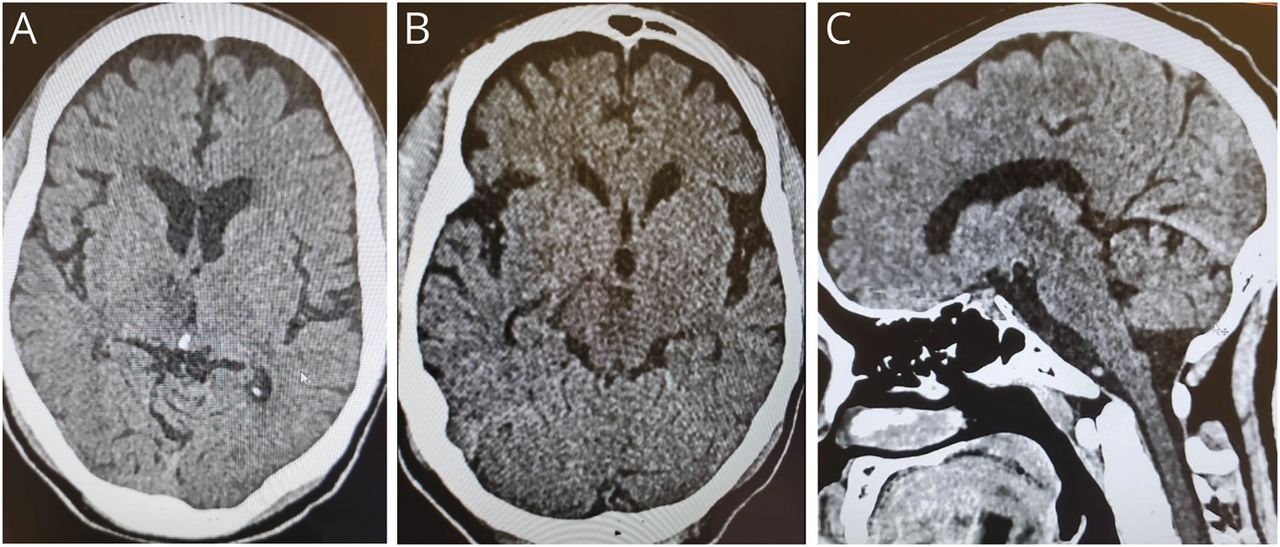

眼部检查结果见图1,A和B.

如在图1一个,双眼上眼睑内缩(左>右),粗斜视(右瞳孔7mm,左瞳孔3mm)。右瞳孔对直接或一致的光反应和尝试收敛没有反应。左眼严重屈光度下降20棱镜(图1一个).双眼完全上视麻痹,不对称下视麻痹(右眼>左眼),右眼内收轻微受限(图1 b).

除了研究结果显示图1,A和B,患者有其他眼肌运动异常。患者无法将双眼合拢,向上凝视时未出现合拢-回缩性眼震。娃娃的头部动作没有引起任何眼球运动。低振幅低频水平抽搐性眼震,右注视时右拍,左注视时左拍。也有中幅低频下拍性眼震,向下注视时增加。由于右眼有完全的垂直凝视麻痹,左眼更明显。左眼震也有扭转成分(视频1).